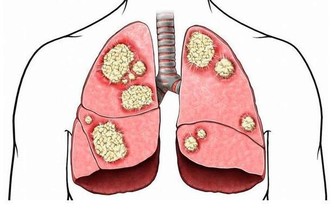

但這些木製品的加工過程中,或使用一些粘合劑,而這些粘合材料中或含超標的甲醛、苯等。

以裝飾畫為例,目前很多裝飾畫的畫框採用的是中密度纖維板,也不乏一些不良商家,使用檔次較低的低密度板,甲醛、苯超標的情況很常見。

而甲醛的危害性,估計不用小編多說了。作為一級致癌物,長時間接觸甲醛,致癌風險也會增加。